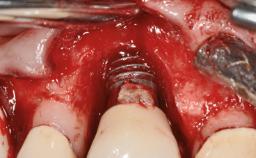

This case describes the ongoing management of a 64-year-old healthy, non-smoking female patient with erosive oral lichen planus (OLP) affecting the gingivae and the buccal and lingual mucosa. The peri-implant mucosa was also affected subsequent to implant placement. The patient had osseointegrated implants (four in the maxilla, four in the mandible) placed following extraction of hopeless teeth and a healing period. The patient had a history of OLP prior to implant placement and had been referred to an oral-medicine specialist for definitive diagnosis and treatment. She exhibited generalized oral mucosal involvement. Following a clinical assessment, biopsy, and blood tests, she was treated with topical corticosteroids. Systemic prednisolone was reserved for severe flare-ups. Amphotericin lozenges were used in combination with corticosteroid treatment to prevent the development of oral candidiasis.

# of Implants 8

Type of Implants Two-Piece